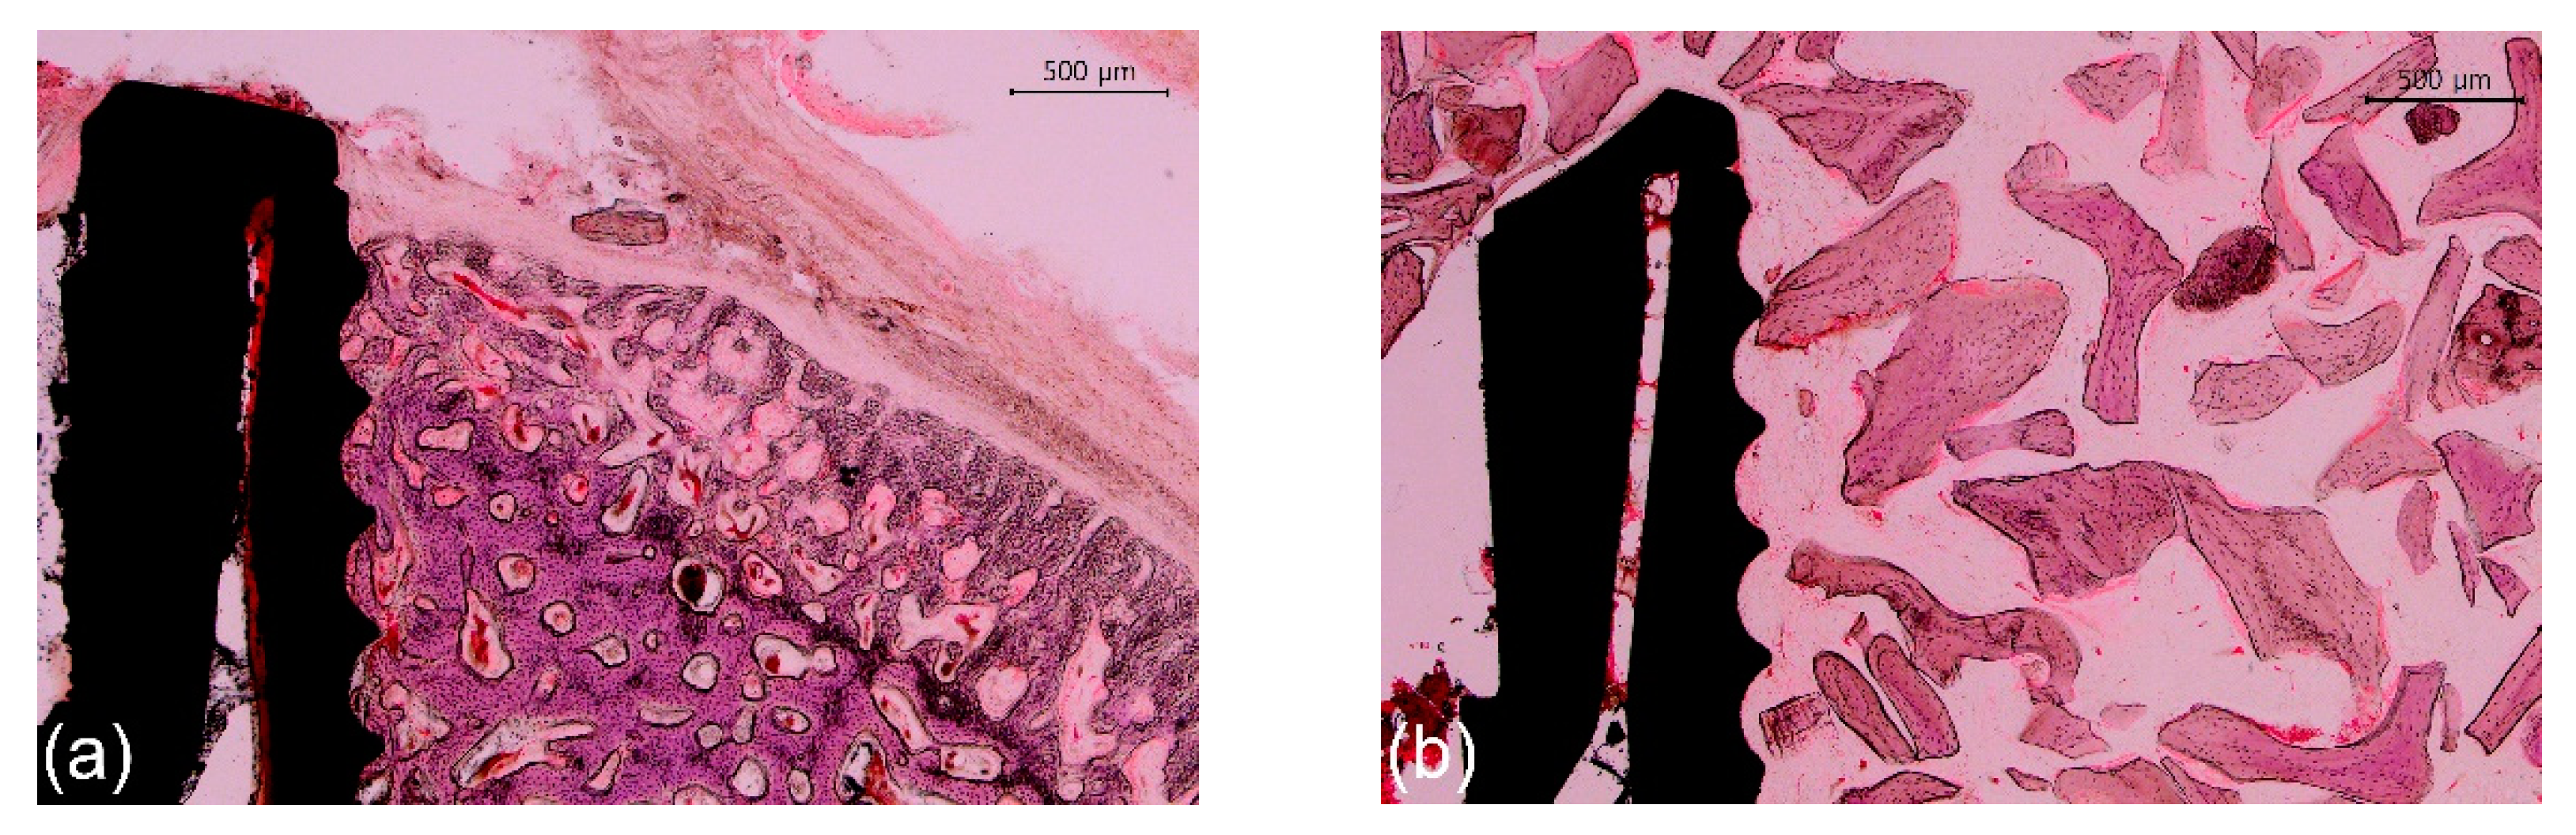

Representative photomicrographs are shown in Figure 6 and Figure 7; the results of the histomorphometric analysis are illustrated in Figure 8, Figure 9 and Figure 10. Apical migration of the epithelium and connective tissue was not observed in any of the samples. In the 2-week group, on the sides with bone grafting, a sparse amount of new bone in the vicinity of the implants was observed in the majority of the specimens, regardless of the method of surface modification used (Figure 7b,d). Therefore, the examiners were unable to perform histomorphometric measurements.

Figure 6.

Representative photomicrographs (12.5× magnification) of hematoxylin- and eosin-stained histological sections of rabbit tibias at the implanted regions. (a) 2-week group; (b) 4-week group. Scale bars: 1000 μm.

Figure 7.

Representative photomicrographs (40× magnification) of hematoxylin and eosin-stained histological sections of rabbit tibias at the implanted regions. (a) Group C-2, nongrafted side; (b) Group C-2, grafted side; (c) Group SU-2, nongrafted side; (d) Group SU-2, grafted side; (e) Group C-4, nongrafted side; (f) Group C-4, grafted side; (g) Group SU-4, nongrafted side; and (h) Group SU-4, grafted side. Note the sparse amount of new bone on the grafted side in 2-week groups. Scale bars: 500 μm.